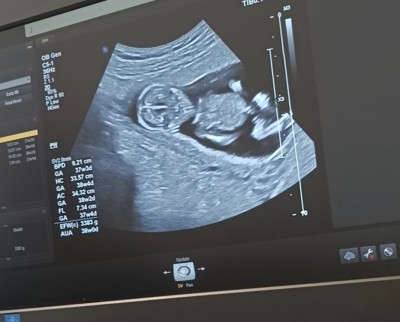

Ultrason görüntüsüne bakarmısınız ultrasonda 12+2suan 13 haftalık sizce kızmı erkekmi

Gebelik haftası 13

imagebanada yorum yapın

Sizinde kız gibi çıkıntı göremedim haftanız büyük doktor cinsiyetini söylemedi mi

Ultrasonda 37+3 görünüyor

önce (11 puan)

Yanlışlık olmuş o zaman nerde yazıyor ben hiç farkında değilim

önce (155 puan)

Sol tarafta tum bilgileri yazıyor kilosu da 3383 gr masallah la havle vela kuvvete illa billah